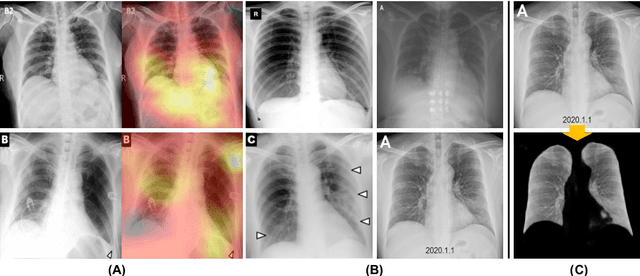

Abstract:We introduce a comprehensive screening platform for the COVID-19 (a.k.a., SARS-CoV-2) pneumonia. The proposed AI-based system works on chest x-ray (CXR) images to predict whether a patient is infected with the COVID-19 disease. Although the recent international joint effort on making the availability of all sorts of open data, the public collection of CXR images is still relatively small for reliably training a deep neural network (DNN) to carry out COVID-19 prediction. To better address such inefficiency, we design a cascaded learning strategy to improve both the sensitivity and the specificity of the resulting DNN classification model. Our approach leverages a large CXR image dataset of non-COVID-19 pneumonia to generalize the original well-trained classification model via a cascaded learning scheme. The resulting screening system is shown to achieve good classification performance on the expanded dataset, including those newly added COVID-19 CXR images.